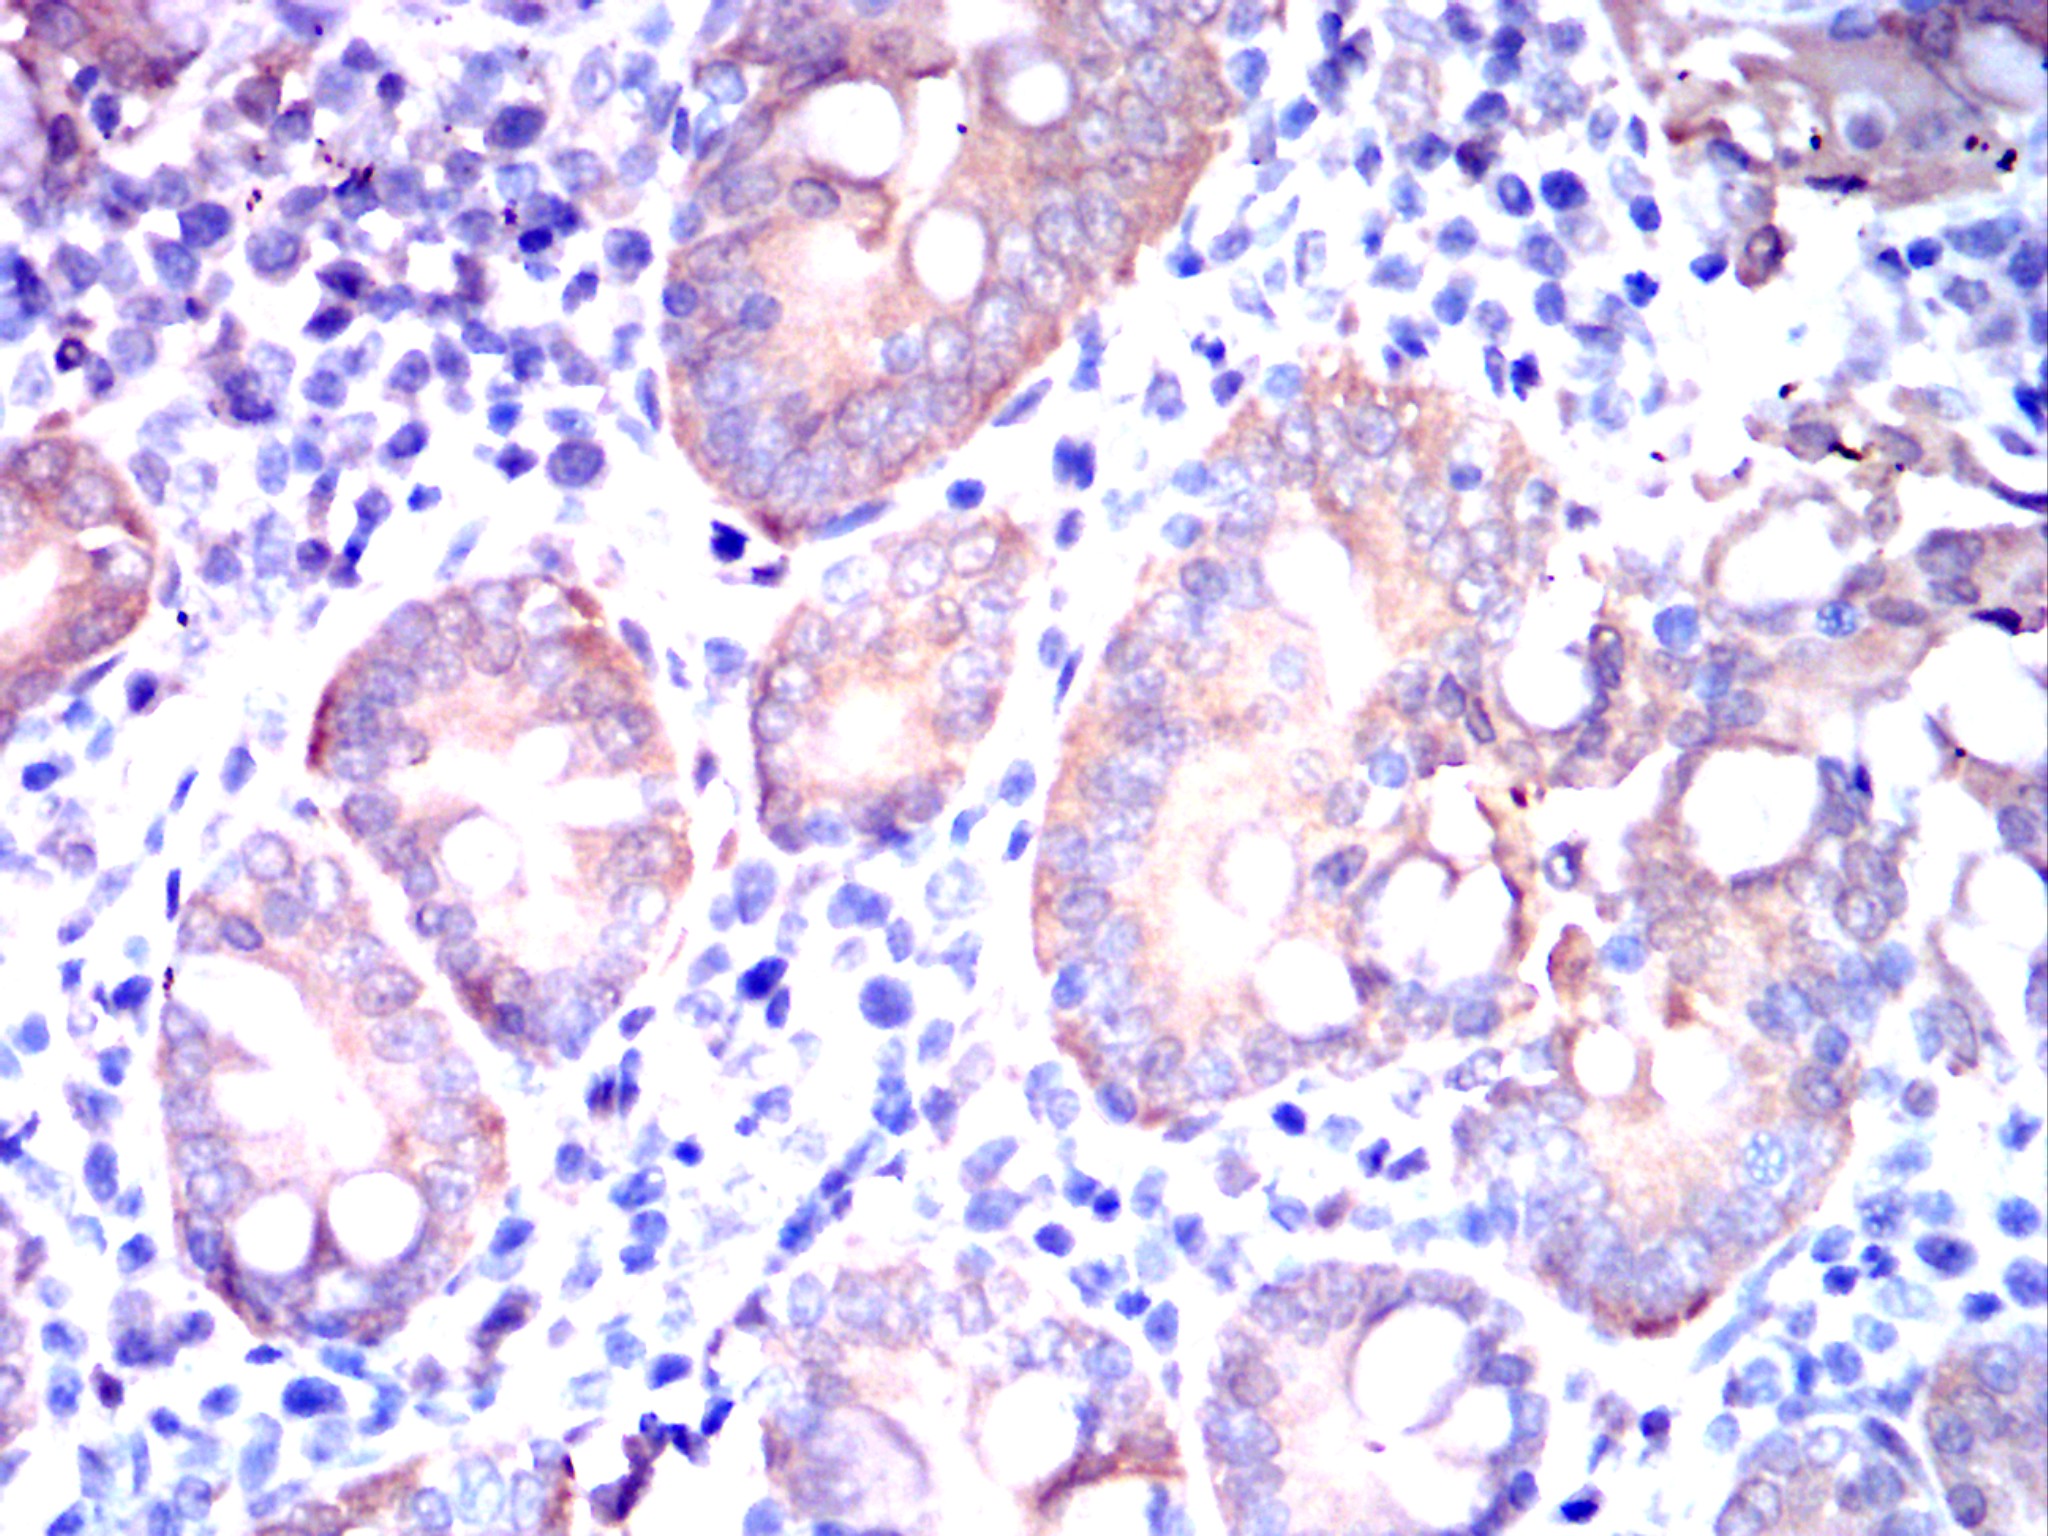

Immunohistochemical analysis of paraffin-embedded human gastric cancer tissues using AKR1C1 mouse mAb with DAB staining.